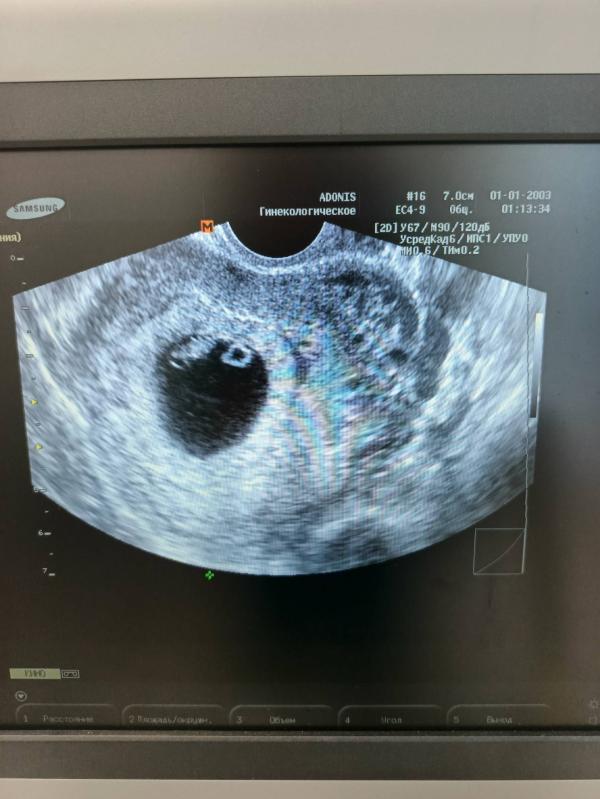

Сходила сегодня на узи , услышала сердцебиение, рада как слон 🤭 как будто впервый раз 🤣

Гематомы нет , хотя на прошлом узи была , куда делась непонятно. Так что растем дальше 🤗

По узи срок ставят 7 недель и 1 день, прям как по месячным 😁